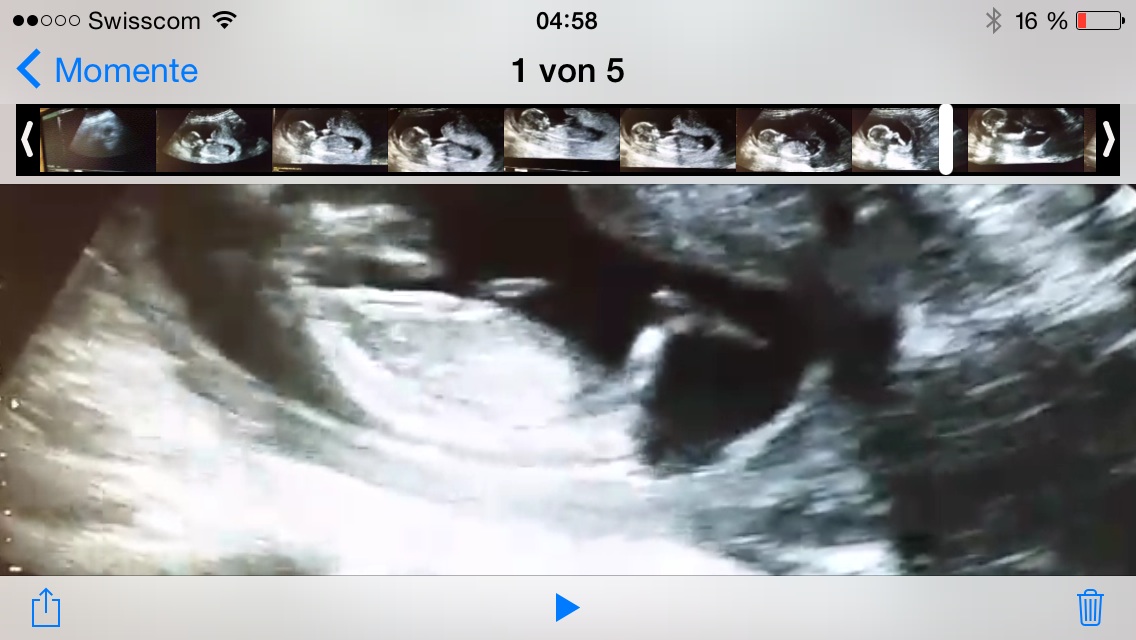

Its that a nub? What you think? Pleas help:bowdown:Attachment 21495

Its that a nub???Attachment 21497

How many weeks? The top looks pink the second looks blue. I am going to lean blue